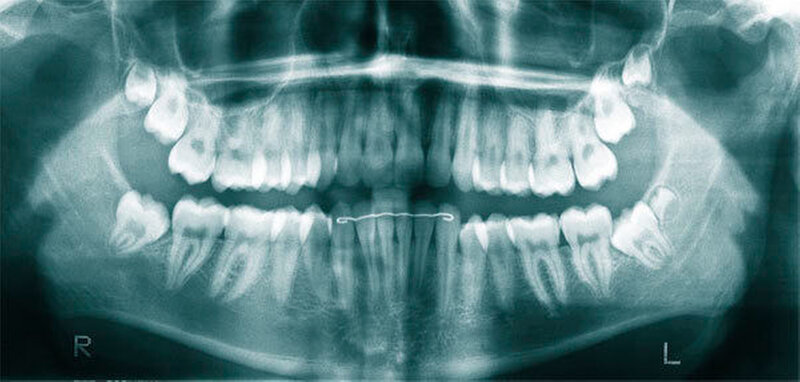

Überzählige Zähne können einzeln oder multipel auftreten [von Arx, 1990; Rajab Hamdan, 2002; Fernández Montenegro et al., 2006; Liu et al., 2007; Gündüz et al., 2008; Ferrés-Padró et al., 2009; Hyun et al., 2009]. Einzelne überzählige Zähne treten in 65,8 bis 80,5 Prozent, doppelte in 14,5 bis 27,7 Prozent und multiple in 0,6 bis 8 Prozent der Fälle auf [Rajab Hamdan, 2002; Fernández Montenegro et al., 2006; Liu et al., 2007; Ferrés-Padró et al., 2009; Hyun et al, 2009; Mossaz et al., 2014]. Einzelne oder doppelte überzählige Zähne finden sich typischerweise in der Oberkieferfront [Rajab Hamdan, 2002; Fernández Montenegroet al., 2006; Mossaz et al., 2014]. Multiple überzählige Zähne werden vor allem im Prämolarenbereich des Unterkiefers gefunden [Abbildung 4; YUSOF 1990, Ferrés-Padróet al., 2009; Wang Fan, 2011]. Multiple überzählige Zähne sind zudem oft mit anderen Erkrankungen oder Syndromen assoziiert, dazu gehören Lippen-Kiefer-Gaumenspalten, die cleidokraniale Dysplasie oder auch das Gardner-Syndrom. Bei Patienten mit einer Lippen-Kiefer-Gaumenspalte wird vermutet, dass sich die überzähligen Zähne aus der Fragmentierung der dentalen Lamina bei der Spaltbildung ergeben [Garvey et al., 1999; Wang Fan, 2011].

Überzählige Zähne werden nach ihrer Lage im Zahnbogen und auch aufgrund ihrer Morphologie eingeteilt. Basierend auf der Lage unterscheidet man bei überzähligen Zähnen zwischen Mesiodens (Oberkiefer median), zwischen den zentralen Inzisiven (Abbildungen 5 und 6), einem zusätzlichen Schneidezahn (zentral oder lateral), Eckzahn, Prämolar (Abbildung 7), Paramolar und Distomolar (Abbildungen 8). Mesiodentes werden am häufigsten dia- gnostiziert, wobei Prozentsätze zwischen 38,8 Prozent bis 86,3 Prozent der überzähligen Zähne in der Literatur zu finden sind [Salcido-García et al., 2004/38,8 Prozent, Fernández Montenegro et al., 2006 /46.9 Prozent; Mossaz et al., 2014/48.5 Prozent; Ferrés-Padró et al., 2009/53.2 Prozent; Schmuckli et al., 2010/75 Prozent; Rajab Hamdan 2002/83.2 Prozent; Liu et al., 2007/86.3 Prozent]. Überzählige Prämolaren und seitliche Schneidezähne sind die zweithäufigste Gruppe der überzähligen Zähne. Überzählige Eckzähne, Paramolaren und Distomolaren dagegen gelten als eher selten [Rajab Hamdan, 2002; Salcido- García et al., 2004; Liu et al., 2007; Ferrés-Padró et al., 2009; Schmuckli et al., 2010; Mossaz et al., 2014]. Einzig eine Spanische Gruppe [Fernández Montenegro et. al., 2006] berichtete, dass Paramolaren und Distomolaren insgesamt relativ häufig seien (18 Prozent, beziehungsweise 5,6 Prozent). Überzählige Zähne kommen im Ober- und Unterkiefer vor, wobei sich überzählige Schneidezähne in der Regel im Oberkiefer, überzählige Prämolaren sich dagegen eher im Unterkiefer befinden [Fernández Montenegro et al., 2006; Ferrés-Padró et al., 2009; Mossaz et al., 2014]. Überzählige Molaren wiederum treten normalerweise im Oberkiefer auf [Cassetta et al., 2014; Kaya et al., 2014].